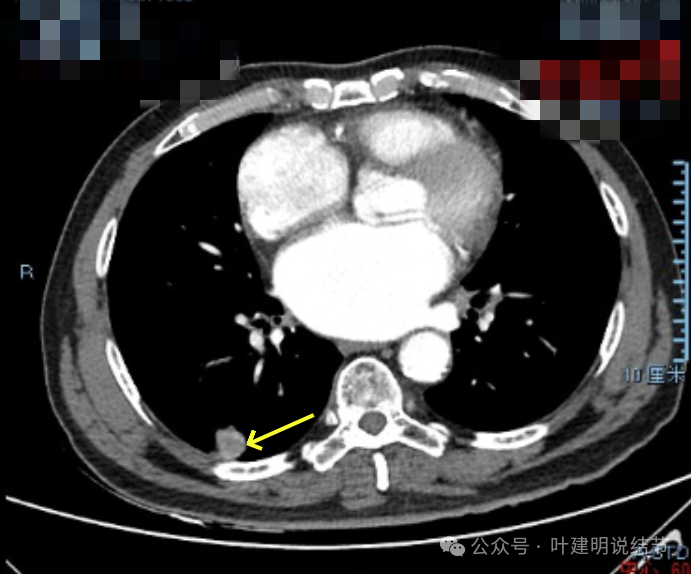

增强纵隔窗见病灶内部的密度好像低于周围区域,像坏死。

邻近胸膜无牵拉,灶内有低密度区,局部有点状液性密度。邻近胸膜较为广泛的增厚或胸膜反应。

病灶与胸膜接触面宽,病灶内部密度较低。